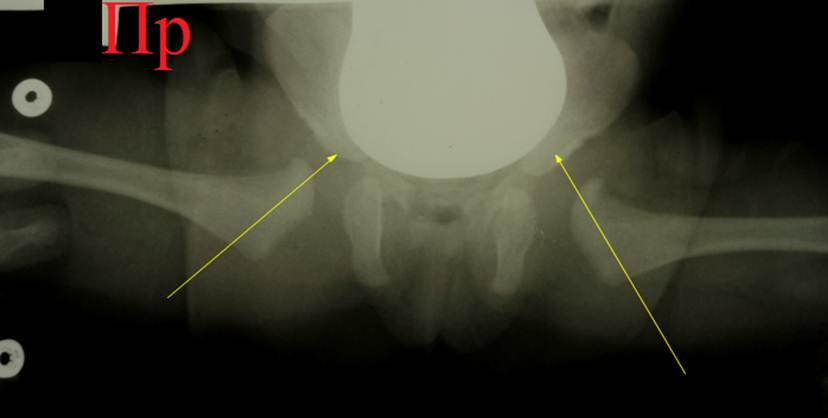

Тот

же ребёнок. Уже через неделю ортезирования ножки приняли положение Лоренц I. Сделан снимок с ортезом: оси шеек обеих бедер чётко

направлены в центр вертлужных впадин, подтверждено вправление головок обеих

бедер. Использование ортеза продолжено

еще 3 месяца.

Предыдущий

снимок мы специально расчертили по

Хильгенрейнеру: показатели центрации головок не в норме, хотя ядра окостенения

находятся кнутри от линий Омбредана – Перкинса. Потому не следует применять

схемы Хильгентейнера и Рейнберга для определения центрации головок на снимках в

ортезе.